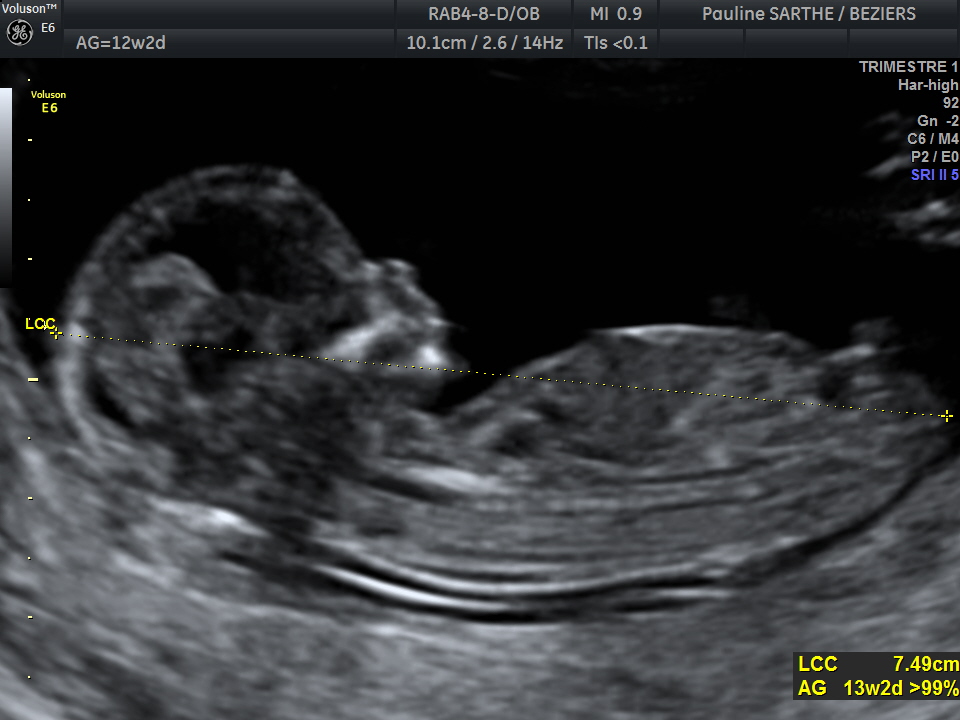

- l'échographie du premier trimestre , réalisée entre 11 et 13 semaines d'aménorrhées et 6 jours, permet de confirmer la date de début de grossesse et donc de votre accouchement, le nombre de foetus et d'effectuer un premier bilan morphologique. Vous pourrez voir votre bébé bouger et entendre son coeur : c'est un moment très émouvant!

L'examen comprendra enfin une mesure très précise sur le fœtus de profil, de la clarté nucale. Celle-ci, associée avec les prélèvements sanguins recommandés mais non obligatoires (Ht 21, PAPP-A) permettra au laboratoire de vous proposer un risque compte tenu de votre âge, pour le dépistage des trisomies 21,13 et 18.